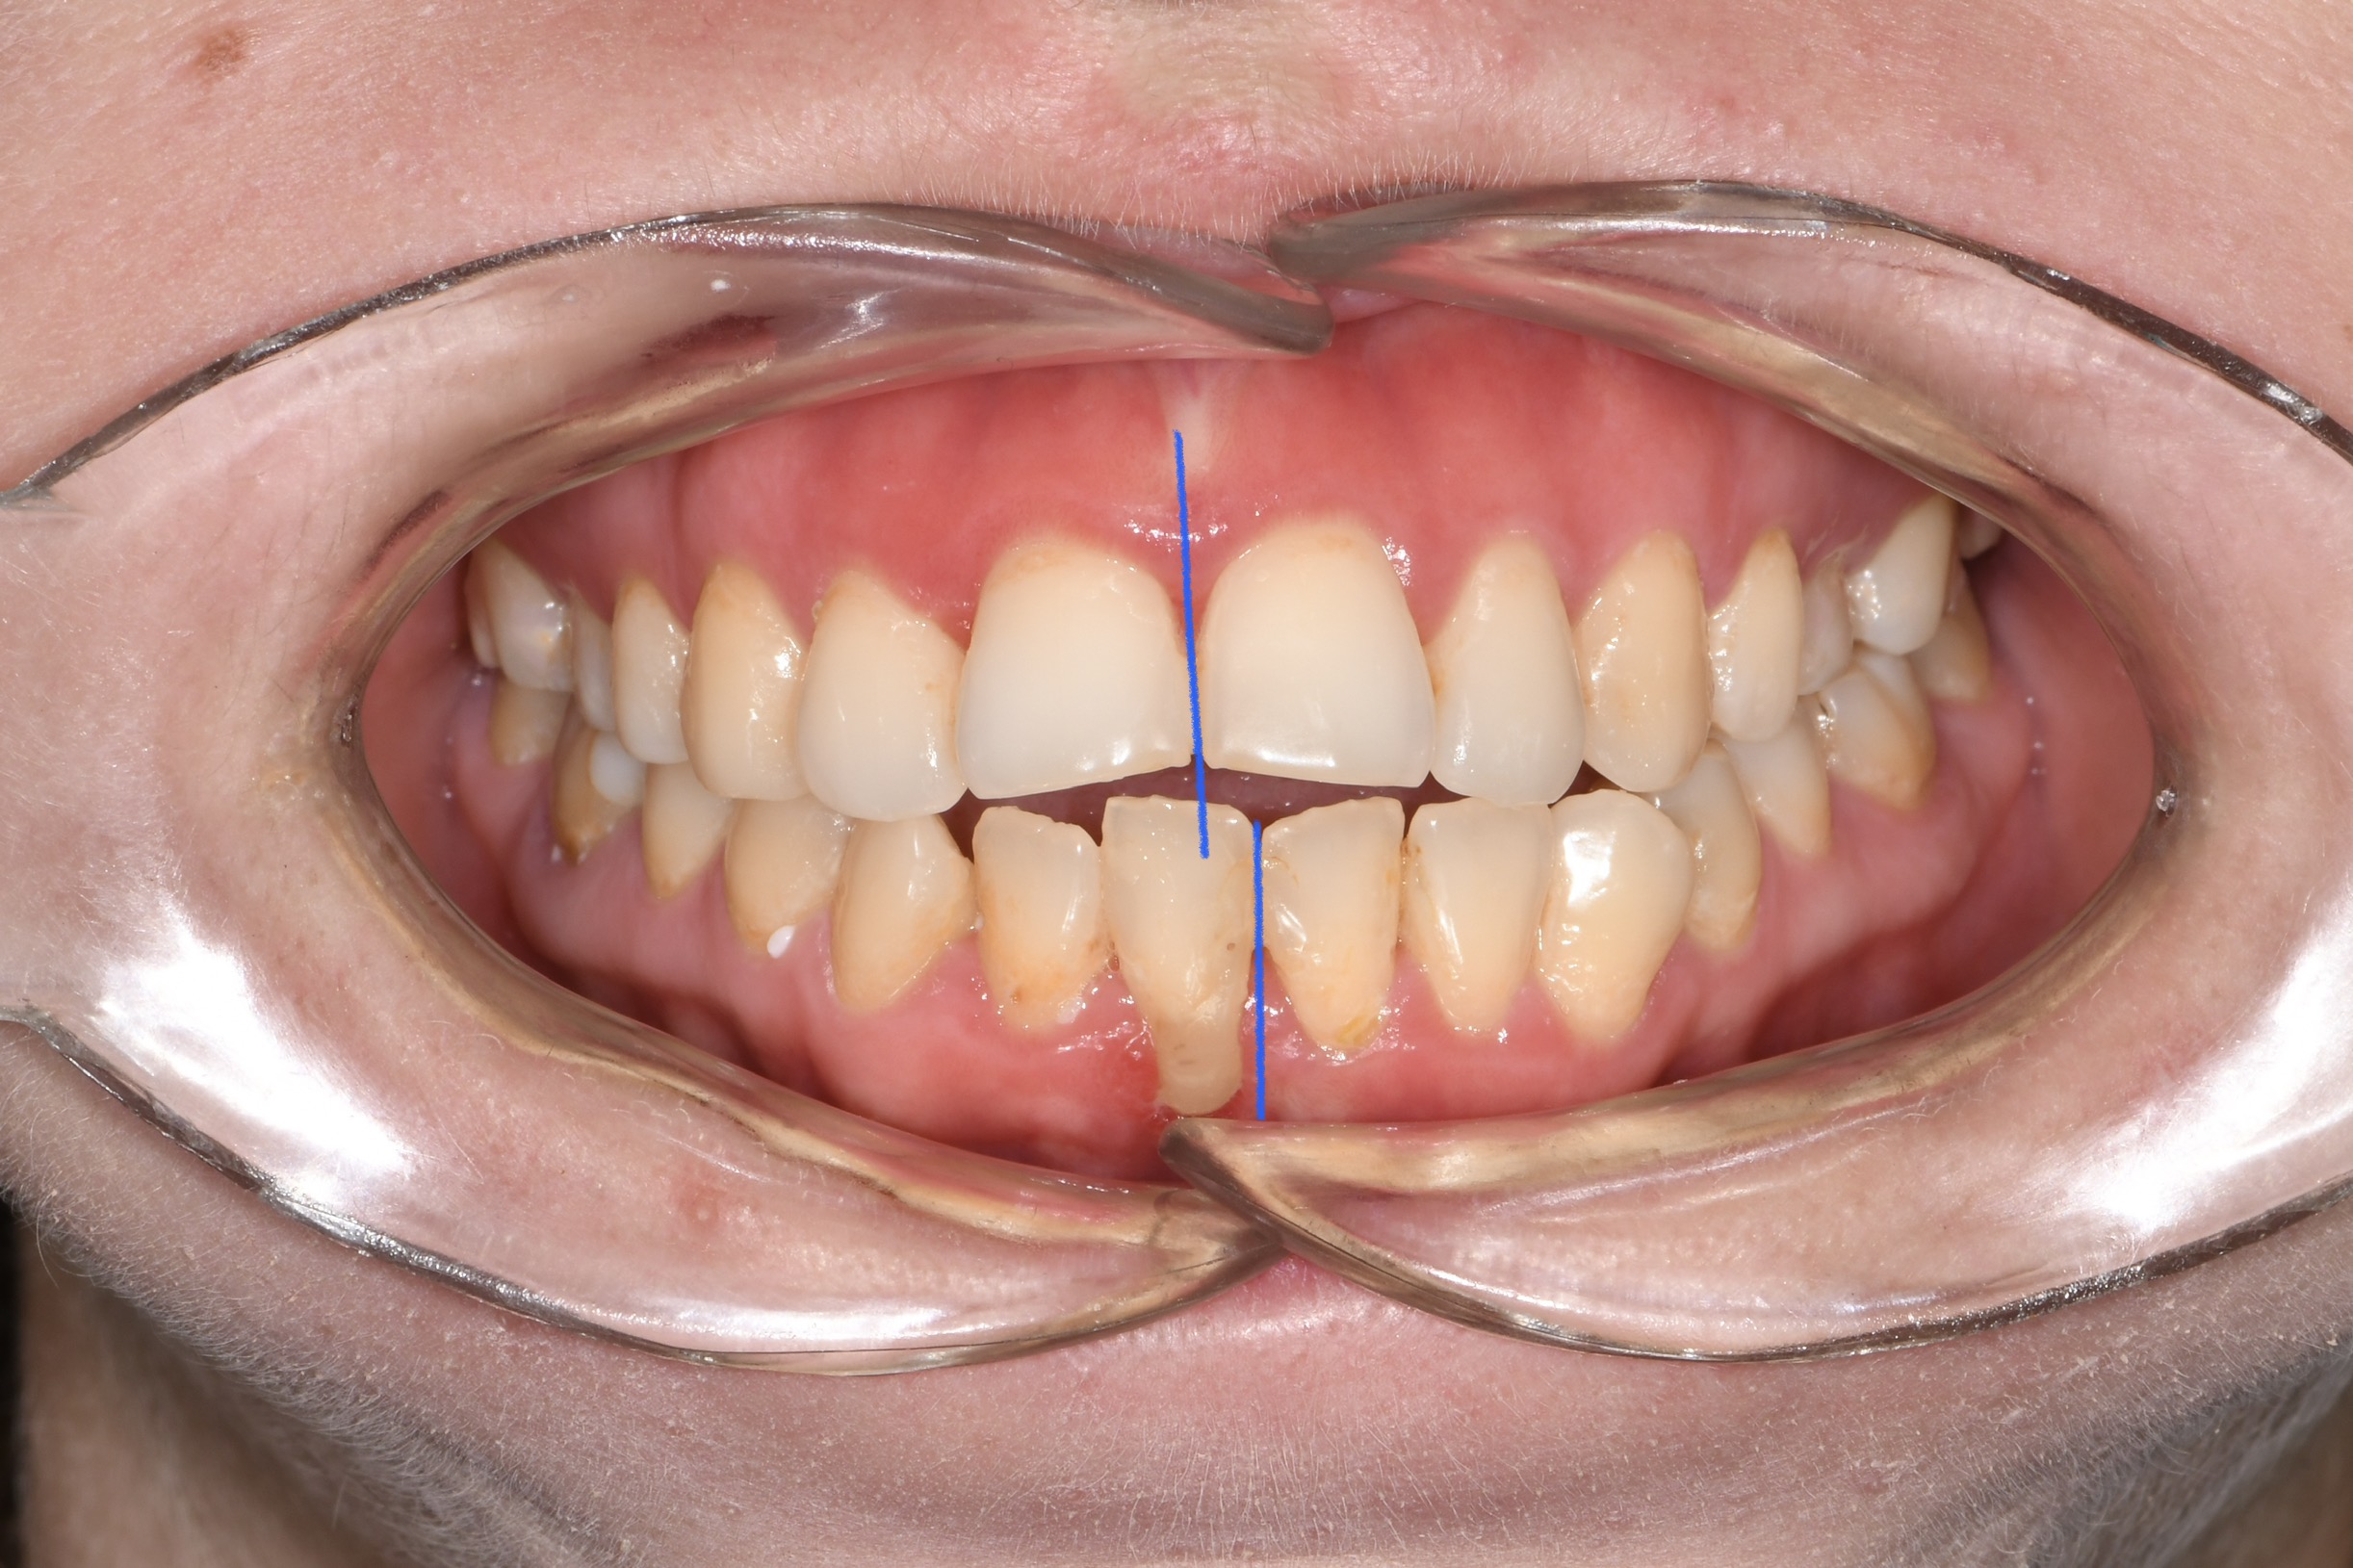

Az elmúlt évekből rengeteg szakmai referenciát tudnánk bemutatni, amelyek különböző fogszabályozási problémákat oldottak meg. Válogatva a több száz esetből, ezen az oldalon olyan képeket, információkat igyekeztünk bemutatni, amelyeknek a segítségével a jövőbeni pácienseinknek azt tudjuk üzenni: A Te fogsorod is lehet gyönyörű!

(Képeket a Pácienseink külön írásos beleegyezésével mutatjuk be!)